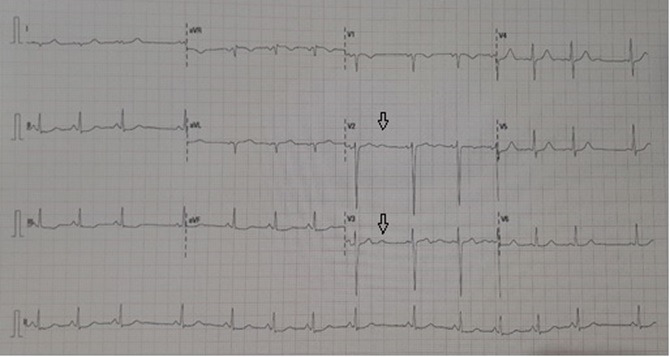

Ante la persistencia de la clínica y afectación del estado general, se repiten nebulizaciones de salbutamol, inmediatamente tras las cuales presenta episodios de mareo con palidez cutánea, decaimiento, taquipnea e hipotensión. Dada la mala evolución se solicita radiografía de tórax sin alteraciones significativas, y un electrocardiograma (Fig. 1) en el que se objetiva una onda U y alteraciones inespecíficas en la repolarización. Se realiza un control gasométrico que evidencia de empeoramiento respecto al previo mostrando acidosis metabólica con hiperlactacidemia y anion gap aumentado.

| Figura 1. Electrocardiograma: onda U (flecha en la imagen) y alteraciones inespecíficas en la repolarización, como efecto del salbutamol |